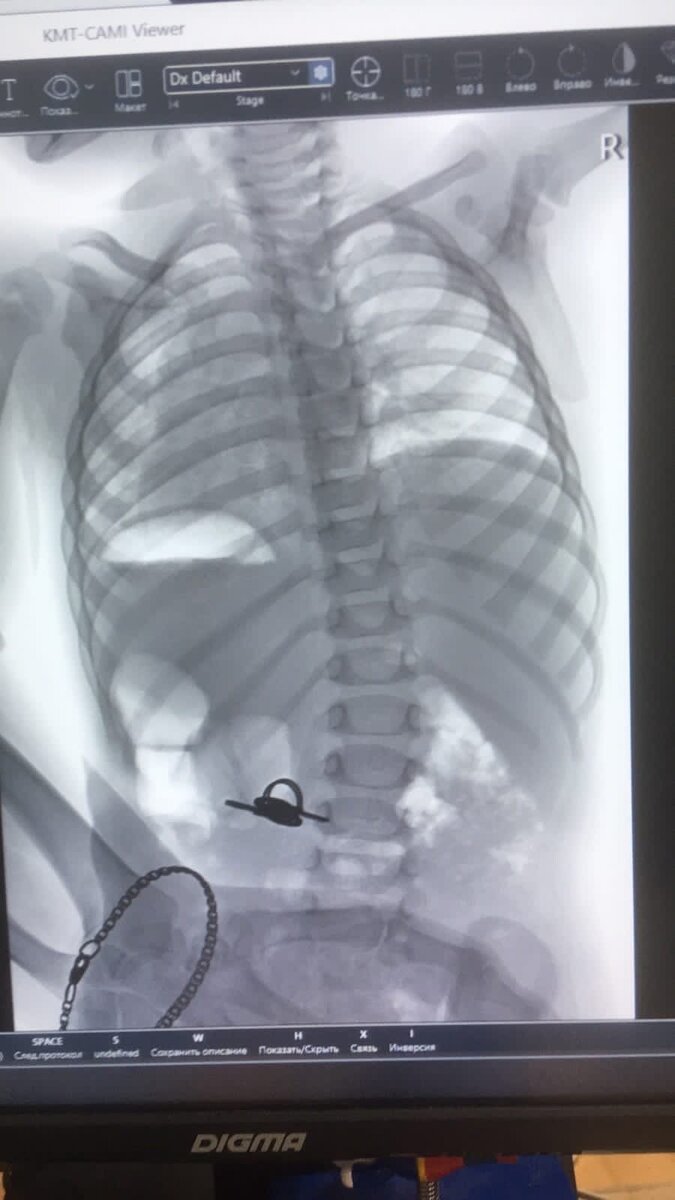

На снимке видны ключи в желудке, а также браслет на маминой руке (девушка придерживала ребенка во время снимка)

На снимках полуторагодовалый ребенок, который решил проглотить связку ключей. Малыша в больницу привезли обеспокоенные родители, которые заметили, что мальчик что-то засовывает в рот. История закончилась хорошо, врачи-эндоскописты Челябинской областной детской клинической больницы под чуткой заботой анестезиологов извлекли ключи из желудка ребенка. Связка, к счастью, оказалась не такой большой - ключи предназначались для открытия почтового ящика.